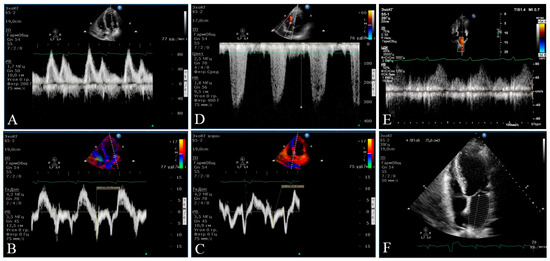

2.3. Instrumental Methods